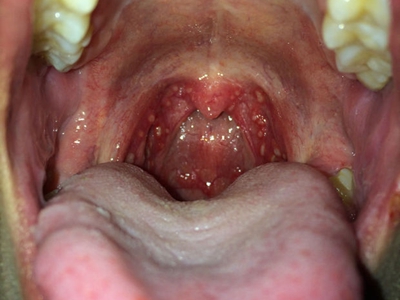

化脓性扁桃体炎扁桃体红肿有白色疙瘩图

化脓性扁桃体炎咽部两侧扁桃体肿大明显,有红枣大小,咽部变狭窄,肿大的黏膜表面有突出的小疙瘩,另外还嵌有形状不规则的白色物质,伴有疼痛,吞咽时更加明显。